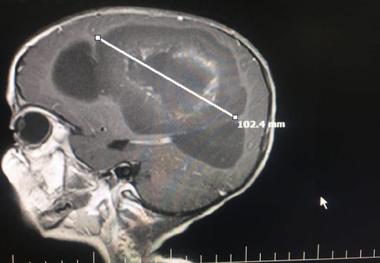

• خارج کردن تومور مغزی 10 سانتیمتری از سر کودک قزوینی

خارج کردن تومور مغزی 10 سانتیمتری از سر کودک قزوینی